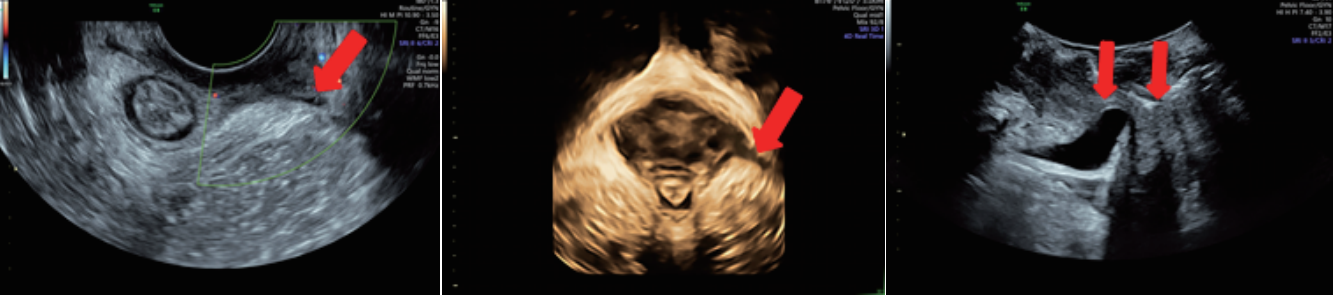

廣泛應用于婦產超聲臨床領域,尤其在產科、不孕不育生殖醫(yī)學和女性盆底功能障礙性疾病等領域,提供高品質圖像及專業(yè)的婦產超聲臨床解決方案。

女性產后盆底功能檢查